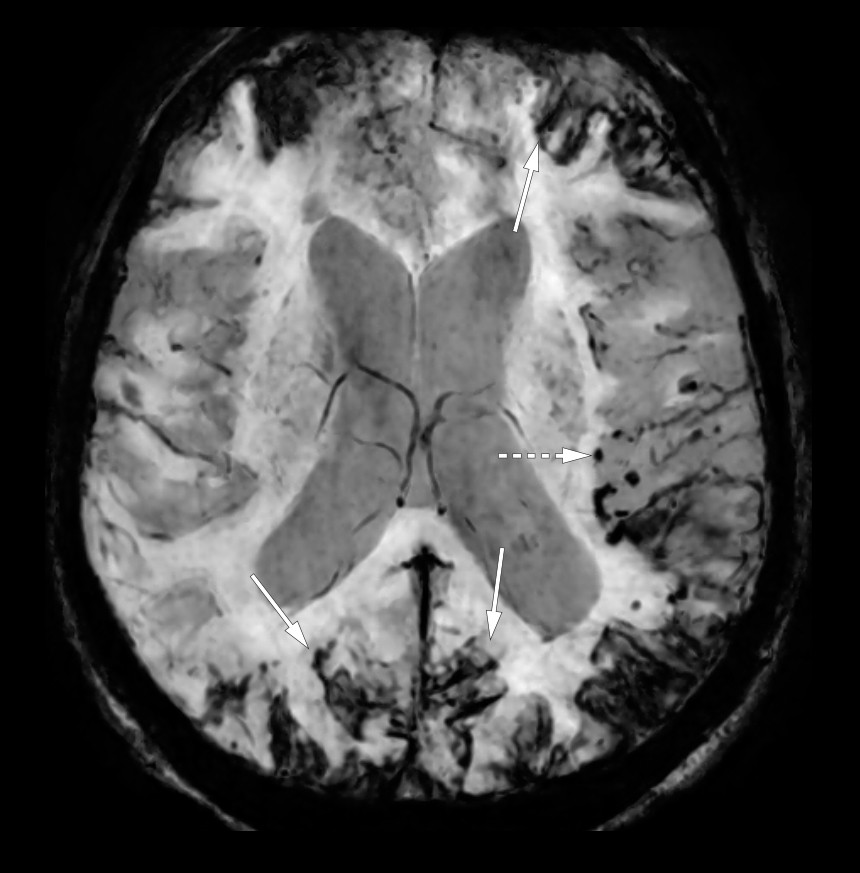

Susceptibility-weighted MRI in the axial plane showed extensive hemosiderin deposition on the facies cerebralis (solid arrows), consistent with superficial hemosiderosis, numerous microhaemorrhages in the brain parenchyma (dotted arrow), most of these subcortically in the left hemisphere. Microhaemorrhages in connection with a previous haemorrhage are typical of amyloid angiopathy.